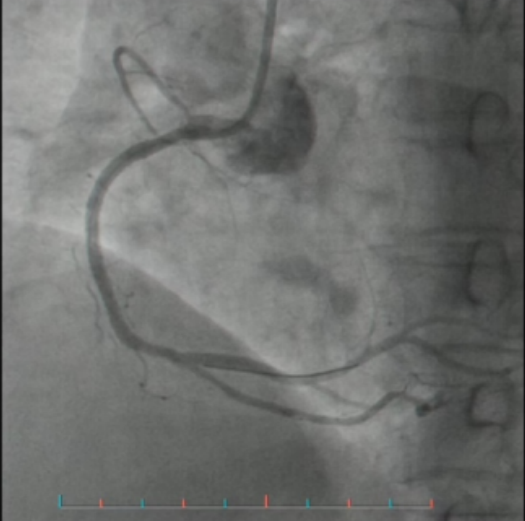

第二天,她前往湖南省中西医结合医院(湖南省中医药研究院附属医院)就诊,心电图结果令人震惊:急性心肌梗死。心血管内三科陆胜主任医师团队迅速为她进行冠脉造影并开通堵塞血管。手术成功,彭阿姨转危为安。

(▲支架术后血流恢复)